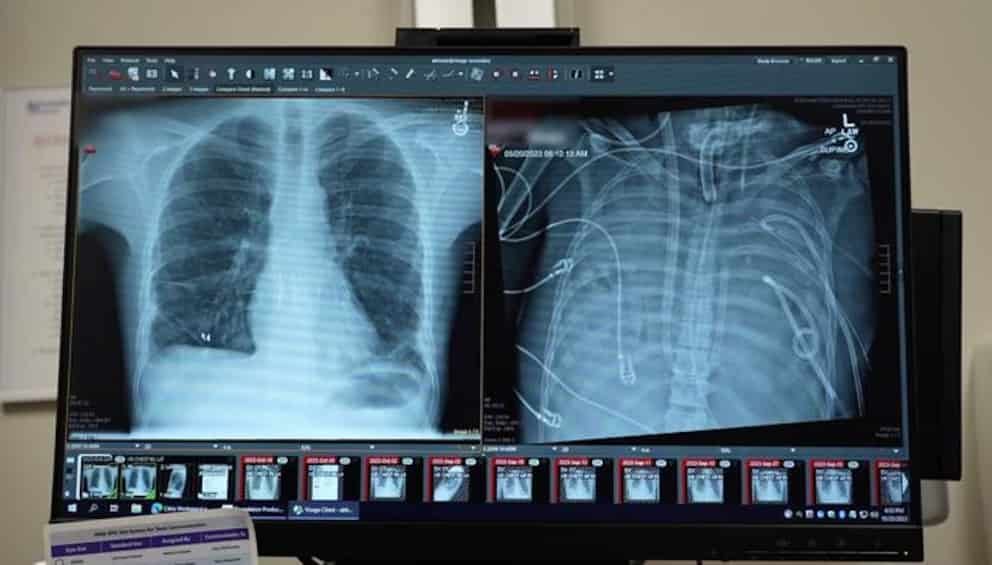

La medicina crítica en Estados Unidos ha marcado un hito con un procedimiento que parecía impensable hasta hace poco. Un joven logró sobrevivir durante 48 horas sin pulmones funcionales gracias a un órgano artificial diseñado para reemplazar temporalmente la función pulmonar. El caso representa un avance significativo en el tratamiento de infecciones pulmonares extremadamente graves y abre una nueva perspectiva para pacientes que, hasta ahora, enfrentaban un pronóstico fatal.

El procedimiento permitió estabilizar al paciente mientras su organismo se recuperaba de una infección severa. La clave fue un sistema artificial capaz de asumir el intercambio de oxígeno y dióxido de carbono, funciones vitales que normalmente realizan los pulmones y que, en este caso, se encontraban completamente comprometidas.

El sistema utilizado fue diseñado para sustituir de forma temporal la función de los pulmones, permitiendo que la sangre del paciente se oxigenara fuera del cuerpo. Durante 48 horas, este órgano artificial asumió una tarea esencial: mantener el equilibrio respiratorio necesario para sostener la vida.

A diferencia de otros soportes respiratorios conocidos, el dispositivo permitió prescindir por completo de los pulmones durante un periodo prolongado. Este enfoque brindó al organismo el tiempo necesario para combatir la infección sin la carga de unos pulmones gravemente dañados.